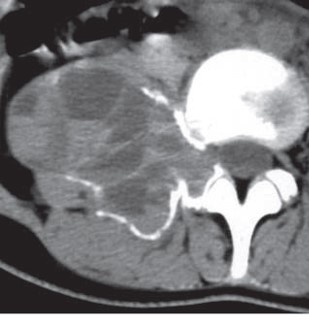

• CT

• T2WI